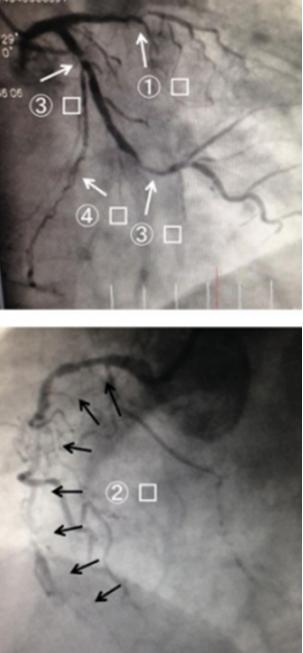

说罢,马修拿起了患者的心电图(图1),V1-V4导联ST段抬高,提示急性心肌梗死。

图1 入院心电图又有学生发问:“马老师,心电图既然已经诊断急性心梗,现在为啥不去做造影?”

马修说:“心电图只是在‘提示’心梗,而不是‘诊断’心梗,……等多种疾病都可以导致心电图出现类似心梗的ST段抬高,所以需要完善鉴别。这些线索马上就要汇总过来了!”

冠脉造影显示三支病变,前降支近段闭塞、回旋支近中段狭窄90%,右冠脉中段也有90%以上的弥漫狭窄。术中判断前降支为罪犯血管,优先进行支架植入处理,择期再处理右冠和回旋支病变。1周之后,患者三支血管均完成血运重建,术后服用阿司匹林、氯吡格雷、阿托伐他汀、卡托普利、卡维地洛,并进行心脏康复治疗。[1]

图2 冠脉造影结果

图3 冠脉PCI术后